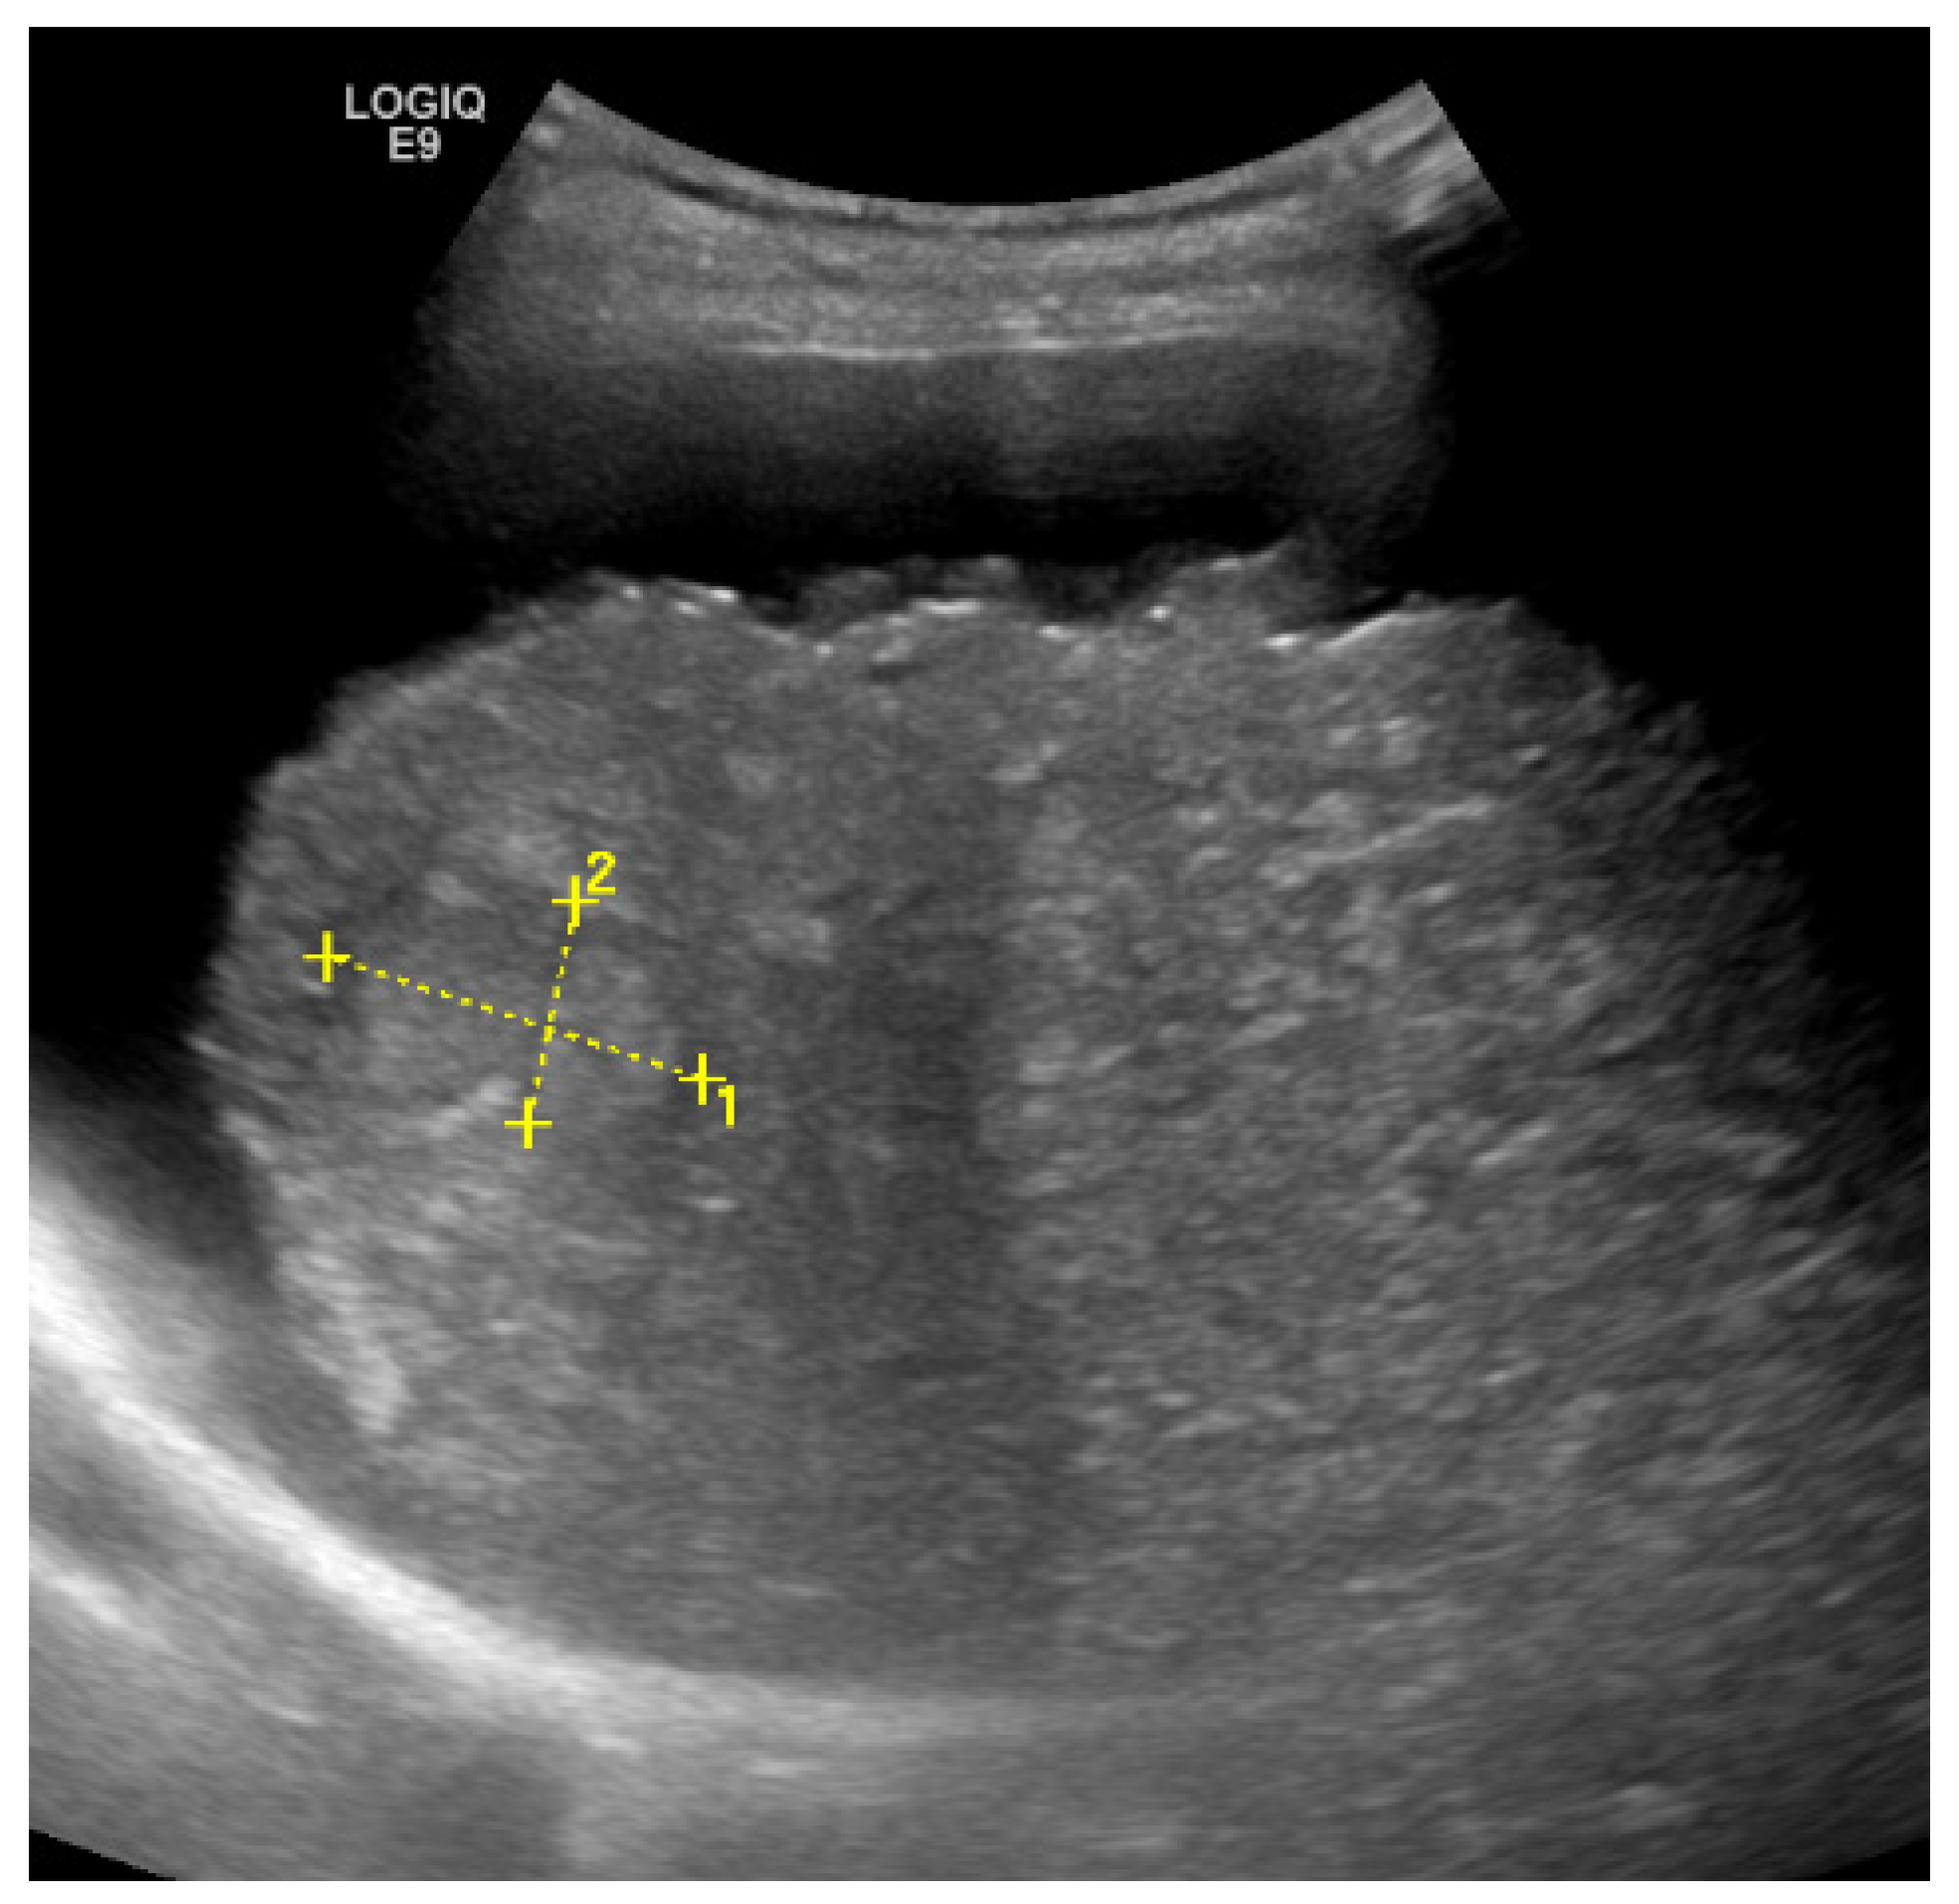

Elastography

| pSWE [41] | F ≥ 2: 69% F ≥ 3: 80% F = 4: 76% | F ≥ 2: 85% F ≥ 3: 86% F = 4: 88% | -integrated in high-end devices, performing in combination with regular US | -smaller ROI |

| 2D-SWE [41] | F ≥ 2: 71% F ≥ 3: 72% F = 4: 78% | F ≥ 2: 67% F ≥ 3: 72% F = 4: 84% | -integrated in high-end devices, performing in combination with regular US -larger ROI (potential more representative) | -high failure rate in obese patients -lack of studies for most devices -lack of defined quality criteria |